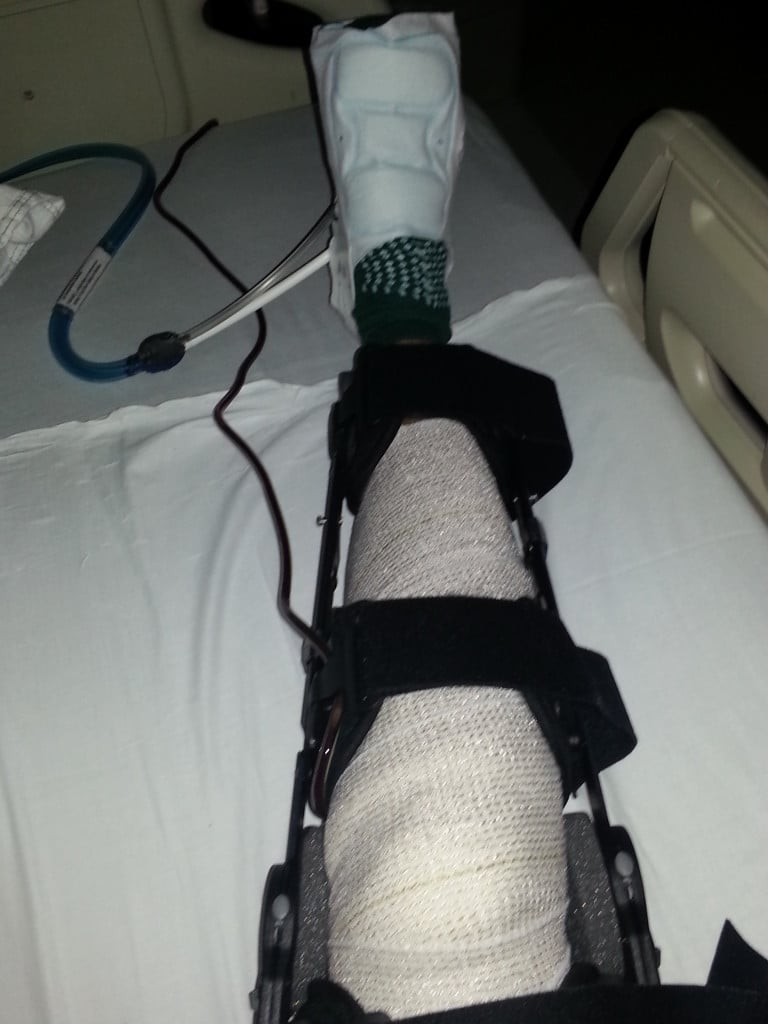

I'm a runner for over 20 years and after I ran the 2011 NYC Half Marathon, I started feeling some discomfort in my right knee, but I did not put too much attention. I went to see an orthopedic MD in Astoria and after an MRI and x-rays, he told me that my days as a runner were over, and that was one of the worst feelings that I ever experienced in my life. To know that running was over for me, I got depressed. After a few months I decided to go for a second opinion and I found Dr. Howard Rose at HSS. He ordered a new MRI. He started a series of cortisone injections that helped with the pain, but still I was not able to run. So in a follow up visit he told me that I was a perfect candidate for Dr. Beth Shubin Stein. He referred me to her and since the first visit I knew that she was the one that could help me. Dr. Shubin Stein and her great team were really honest and straight forward with me and she proposed and explained a procedure that can put me "back in the game." I agreed to do the surgery called Tibial Tubercle Transfer with Denovo implant, which was performed in 12/2012. After a year of the surgery I was running again and after almost 2 years, I ran the 2014 TCS NYC Marathon. I can't found have enough words to express how thankful and blessed I am for had a great surgeon such as Dr. Shubin Stein working on my knee. She is my superhero, my Wonder Woman and I'll be grateful for the rest of my life for to give me back the chance of enjoying  again the passion of running. Thank You HSS!